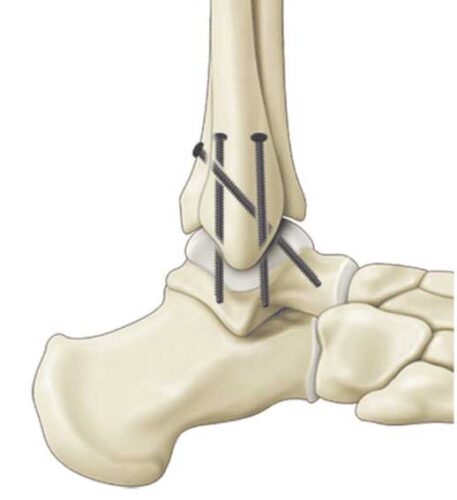

Bone grafting is a surgical procedure in which fractures or cracks in bones are repaired. This is typically done by stabilizing the broken or cracked bone using fixation materials such as surgical screws, plates, wires, or screws. The goal of this procedure is to restore the alignment of the bones and provide the necessary stability to promote proper bone healing.

A bone graft is a surgical procedure used to repair fractures or tears in bones by fixing the damaged bone pieces using plates or surgical screws, usually in the form of a patch on the bone’s surface. Bone grafts help restore bone stability, promote healing, and are used in a variety of cases that require surgical bone fixation, including:

Shin bone fixation surgery is a surgical procedure used to repair fractures or cracks in the bones that make up the shin. This procedure involves stabilizing the fractured bones using surgical screws or plates to restore bone alignment and promote healing. Here are the general steps of shin bone fixation surgery:

- The patient is generally or locally anesthetized, depending on the patient’s condition and surgeon’s preference.

- A surgical incision is made in the skin near the area of the fractured bone to access the bone. The skin and soft tissues are dissected to reach the fracture.

- The surgeon assesses the size of the fracture and the alignment of the bones, determining if any additional procedures such as wound cleaning or fracture reduction are necessary.

- The fracture is corrected using surgical screws or fixation plates, as needed, to ensure bone stability and promote healing.

- After the repair, the incision is closed, either with stitches or surgical staples.

- A dressing is applied to stabilize the area and support the healing process.

- The patient should follow post-surgery care instructions and have regular follow-up appointments with the surgeon to monitor bone healing and regain motion and strength in the shin.